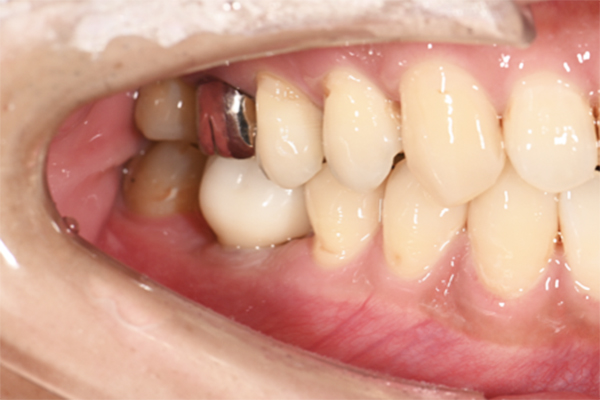

| 主訴 | 右下の奥歯が痛い |

|---|---|

| 治療内容 | 右下奥歯が割れていたため抜歯、その後インプラント治療を行った。(左の写真は抜歯後の写真) |

| 治療期間 | 4ヶ月 |

| 治療費 | 41万5千円 |

| 治療 リスク | 抜歯後インプラントの処置まで3ヶ月程度治癒期間(骨ができるまでの期間)が必要なことがあります。 |